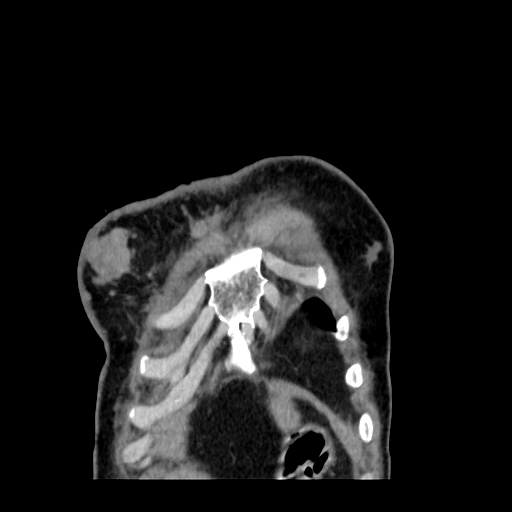

A 62 years old man with enlarged mole on chest since 2 months.

CT chest :-